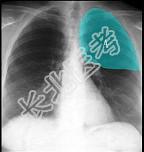

- 单项选择题如图所示正常胸部X线影像图像上,该英文字母所代表的肺段为 ( )

A、尖段

B、后段

C、尖后段

D、舌叶上段

E、前段